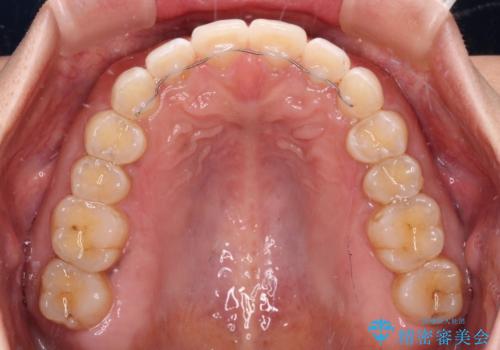

【モニター】前歯のすきっ歯をインビザラインで改善

- 上顎前歯の隙間と口元の突出感を気にして来院された患者様です。

高校生の時に行った矯正治療の後戻りであり、歯列不正は軽度であったので、インビザラインにて治療を行うこととしました。

すきっ歯はあっという間に後戻りを起こすので、可及的に後戻りを防止するために、上下前歯部を舌側からワイヤーで固定しています。

通常は下顎前歯のみに行っていますが、空隙歯列弓では上顎でも行っています。